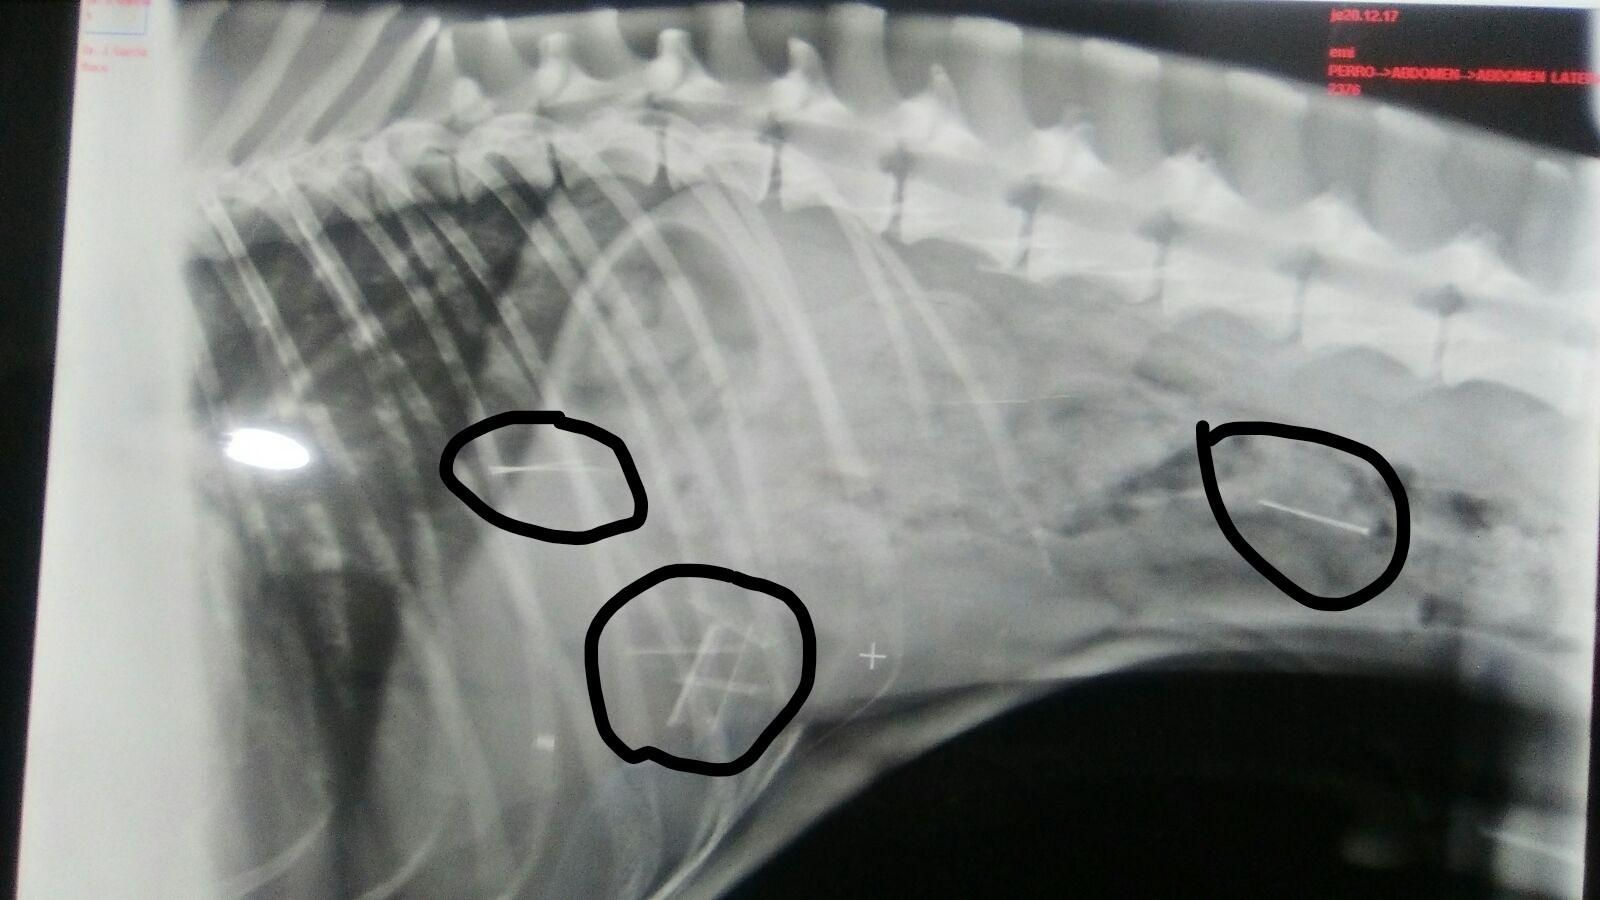

Radiografía de un galgo en la que se aprecian los objetos punzantes.

Radiografía de un galgo en la que se aprecian los objetos punzantes. / D.c.

El de ayer fue el caso de un galgo, Flaco, que llegó a la clínica veterinaria Nueva Tavira con ocho alfileres entre intestino y estómago. Más allá del modo -esconder objetos punzantes en salchichas y dejarlas en la calle para que los animales las coman es una táctica muy recurrente-, el caso de Flaco no es un caso aislado. O eso, al menos, denuncia la plataforma Cádiz Animal, que dio a conocer el incidente: según la asociación, este se suma a varios casos más de los que el grupo ha ido teniendo noticias a lo largo del año. "En abril -comenta su presidente, Ismael Gómez-, contactó con nosotros una chica porque su perra también había comido varias salchichas con clavos, muriendo a consecuencia. A principios de verano, se dieron otros casos por la zona del Pópulo y la Catedral. Y ahora parece que es por el barrio de la Viña, según nos han dicho, por la zona frente a Valcárcel".